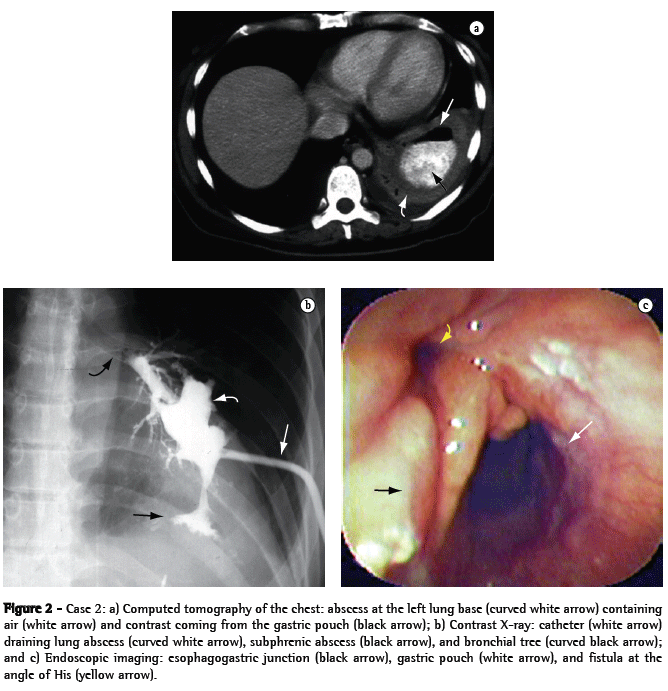

A 44-year-old female patient who underwent vertical banded gastroplasty (sleeve gastrectomy) by laparoscopy developed gastric fistula and presented five episodes of subphrenic abscess over an 8-month period. Her clinical symptoms began with pain in the left shoulder and worsened to include fever, cough, leukocytosis, worsening of overall health status, and excessive weight loss. The last two episodes were accompanied by cough with purulent expectoration, and computed tomography of the chest diagnosed an abscess at the left lung base (Figure 2a), secondary to subphrenic abscess at the angle of His, and gastric stenosis at the level of the band and the incisura angularis. The lung abscess resulting from the gastrobronchial fistula was drained through a catheter seen on a contrast X-ray (Figure 2b), and endoscopic imaging showed the internal opening of the fistula at the angle of His (Figure 2c).

The patient was monitored by a pulmonologist, an endoscopist, and a surgeon. She was treated with antibiotic therapy, respiratory therapy, and nutritional support provided through a nasogastric tube. In addition, the patient underwent exploratory laparoscopy for removal of the band, at which point a severe inflammatory obstruction was seen in the left subphrenic region and in the esophagogastric junction, making it impossible to gain surgical access to the fistula.

Therefore, we carried out six endoscopic stenostomy sessions using an electric scalpel and dilatation of the stenotic area, thereby allowing satisfactory food intake, nutritional recovery, and cicatrization of the lung abscess, after the permanent closure of the fistula.